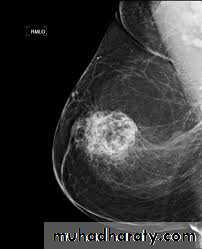

Combining form for Body SystemsReproductive

• mamm/o breast